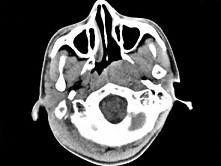

问题 男,17岁,自诉鼻涕中带血3个月,伴耳闷、听力减退,无发热。如图所示鼻咽部病灶最可能的诊断为 ( )

选项 A、小唾液腺混合瘤 B、鼻咽部淋巴组织增生 C、鼻咽部恶性淋巴瘤 D、鼻咽癌 E、咽旁脓肿

答案 D